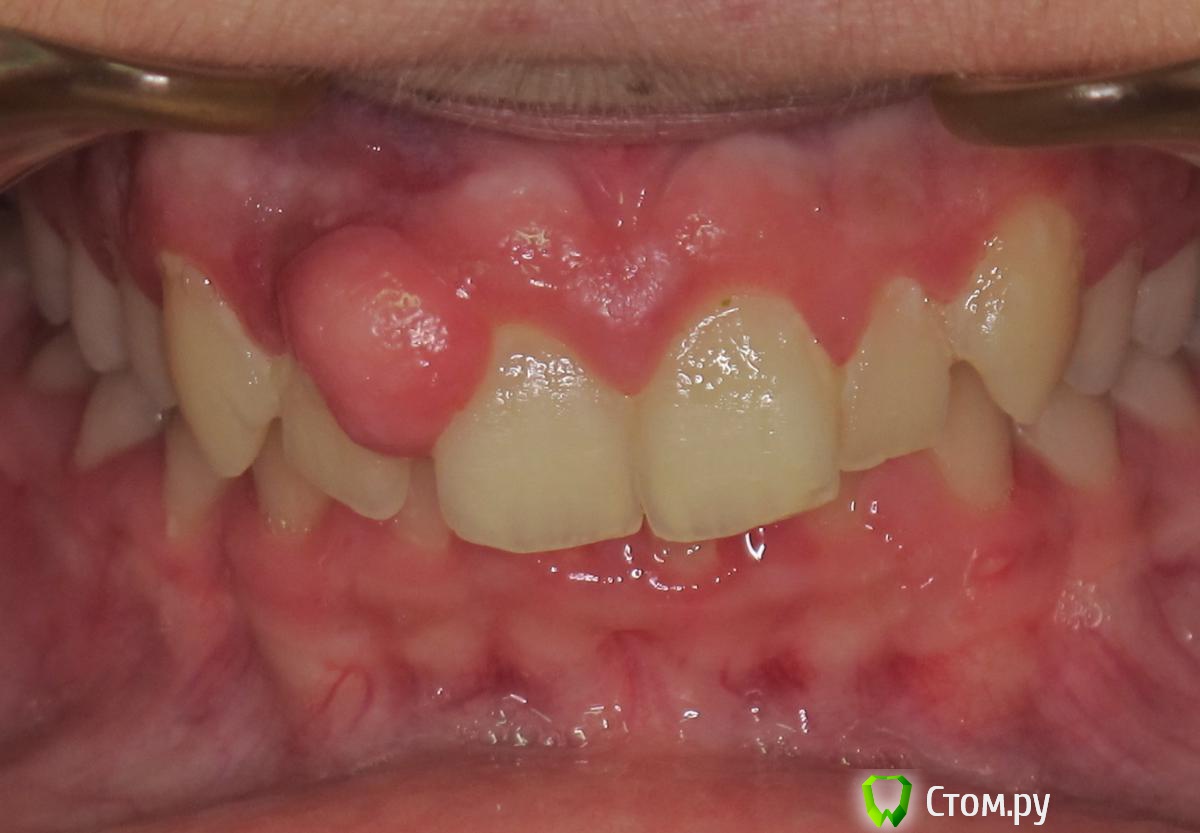

johniola Опубликовано 7 мая, 2014 Поделиться Опубликовано 7 мая, 2014 (изменено) Мальчик 13 лет.Эпулис? Какое мнение у коллег?Простите за фото. Изменено 7 мая, 2014 пользователем johniola Ссылка на комментарий

red_butler Опубликовано 7 мая, 2014 Поделиться Опубликовано 7 мая, 2014 снимок, удалять и на гистологию Ссылка на комментарий

Maxfac Опубликовано 7 мая, 2014 Поделиться Опубликовано 7 мая, 2014 биопсия в первую очередь, затем операция!+1Иногда за похожими штуками скрывается ОБК Ссылка на комментарий

mr.Fog Опубликовано 9 мая, 2014 Поделиться Опубликовано 9 мая, 2014 А образование на ножке, на узкой или широкой? Какое время существует, не чрезвучайно ли использует флос? Соматически здоров? Инцизионная хирургическая биопсия в помощь- в данном случае иссечение с вестибулярной стороны с захватом здоровой слизистой. Тампоном с 3%h2o прижатья, если нет коагулятора. Ссылка на комментарий

johniola Опубликовано 16 мая, 2014 Автор Поделиться Опубликовано 16 мая, 2014 Чем закончилось?Да закончилось, это фиброзный эпулид,уже почикали Ссылка на комментарий

kriokov Опубликовано 16 мая, 2014 Поделиться Опубликовано 16 мая, 2014 Нет,до того.Я его в стационар отфуболил,там и сделали.боковой резец оставили? Ссылка на комментарий

johniola Опубликовано 16 мая, 2014 Автор Поделиться Опубликовано 16 мая, 2014 боковой резец оставили?Вроде ка да,я ещё его не видел 1 Ссылка на комментарий